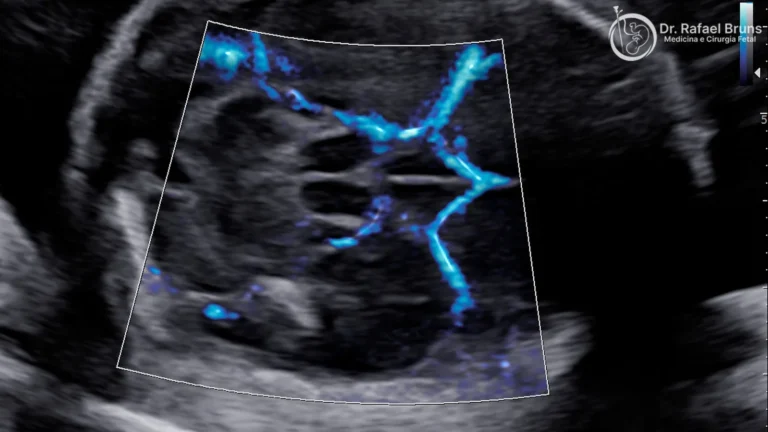

Doppler colorido e avaliação do segmento inferior

O Doppler colorido tem papel central quando há suspeita de acretismo placentário associado. Avalia a vascularização retroplacentária e da interface útero-bexiga, detecta vasos “pontes” entre placenta e bexiga (bridging vessels) e identifica lacunas intraplacentárias — os marcadores ultrassonográficos mais específicos e confiáveis de invasão anormal.

- Hipervascularização e bridging vessels: vasos que atravessam a interface útero-bexiga, identificados pelo Doppler colorido